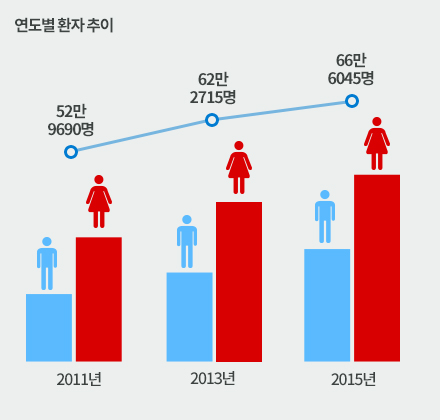

대상포진 환자추이